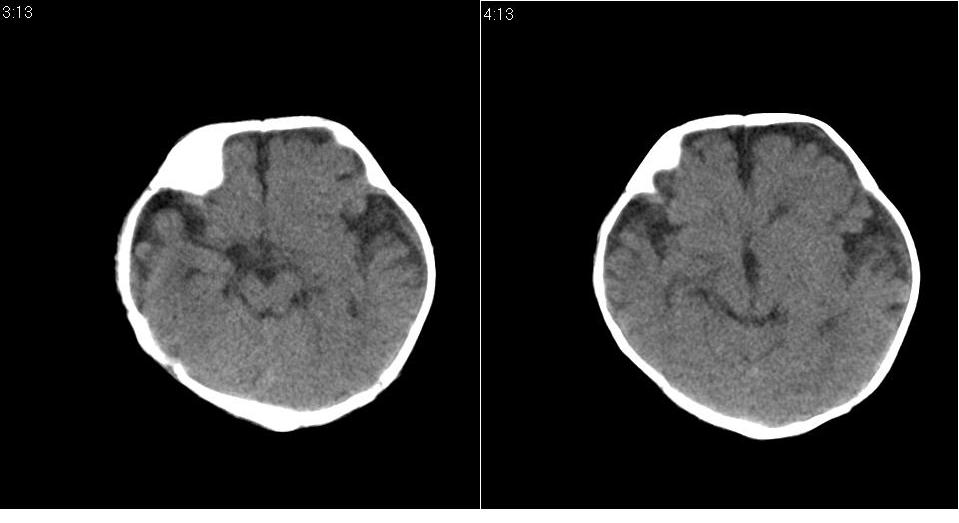

标题: PED1744:颅脑CT平扫

男 3个月,头大,颈软,头向后仰。

外部性脑积水

考虑外部性脑积水。

脑外间隙增宽,未见明显异常。

脑外间隙增宽,余未见明显异常。

脑外间隙增宽,现在好像有人说是一种发育性的交通性脑积水

蛛网膜增宽,外部性脑积水?

外部性脑积水(也就是诸位说的脑外间隙增宽);脑实质内未见异常密度灶,脑室系统无扩张,建议随访,毕竟临床症状听着怪吓人的。